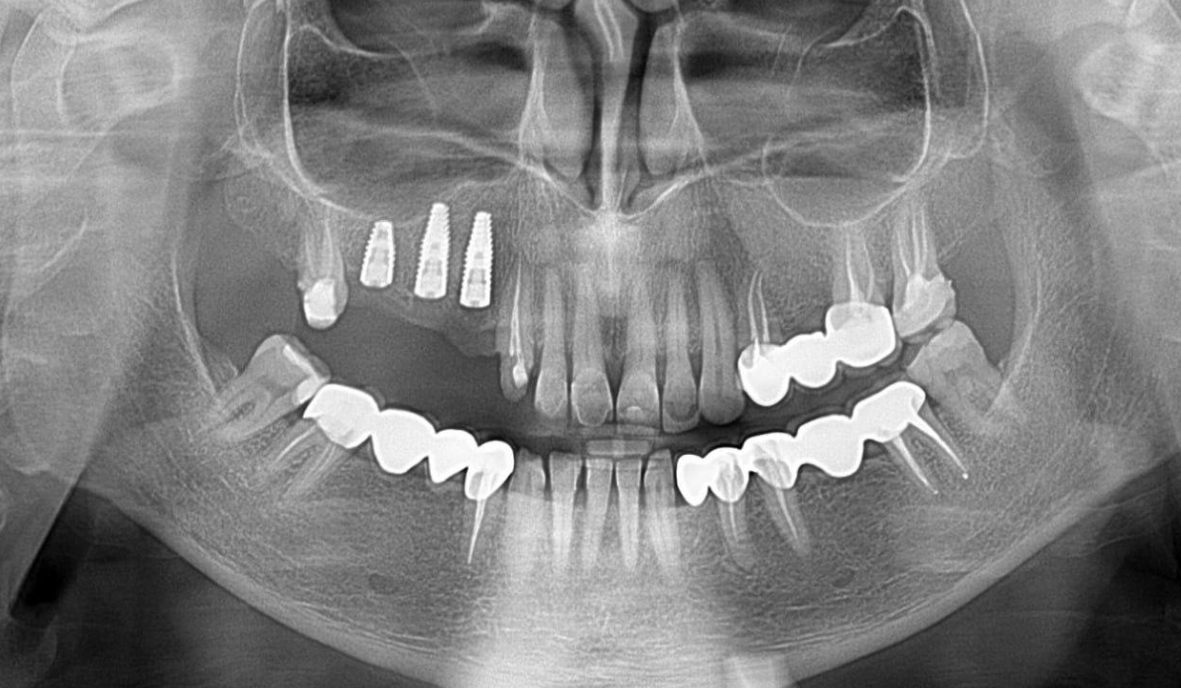

Initial clinical situation

The patient presented with complications related to a PFM bridge supported by teeth 13, 15, and 17. The root of tooth 15 was compromised, causing pain and severe discomfort for the patient.